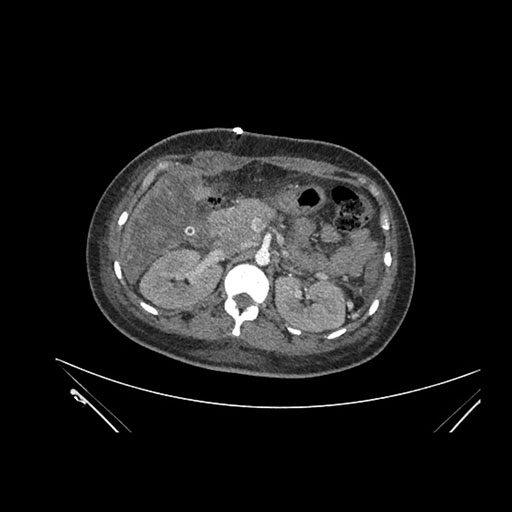

Axial Arterial

Imaging analysis

Based on initial findings, which issue(s) would you be most concerned about?